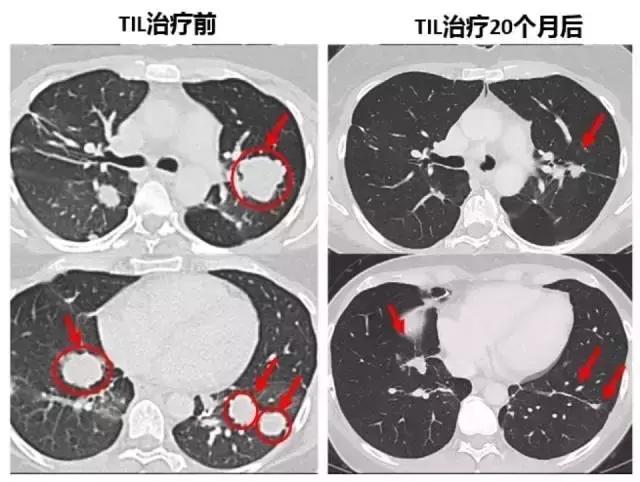

在美国国立卫生研究院(NIH) 领导的研究中,TIL治疗产生持久的反应,包括转移性宫颈癌的完全消退。该研究中有9名女性中有3名有响应,包括2名完整响应(CR)和1名部分回应。客观反应率为33%,在NIH的试验中,没有发生与细胞输注有关的毒性发生。

一名患有转移性鳞状细胞癌并接 受了多种联合化疗方案,包括顺铂,长春新碱和博来霉素,然后用吉西他滨加顺铂联合放疗。随后发现转移,包括主动脉旁,双侧肺门,颅下和髂骨部位(图1A和1C)。治疗后,她在所有疾病部位都完全消退(图1A和1C)。

另一患者患有转移性腺癌。她的 原发性肿瘤对化放疗无效。随后转移到更多的腹膜后淋巴结和肝脏表面,在TIL治疗前,她在腹膜后,腹壁,旁系,肝旁和盆腔部位有肿瘤进展(图1B和1d)。在治疗后,出现完全的临床缓解(图1B和1d)。